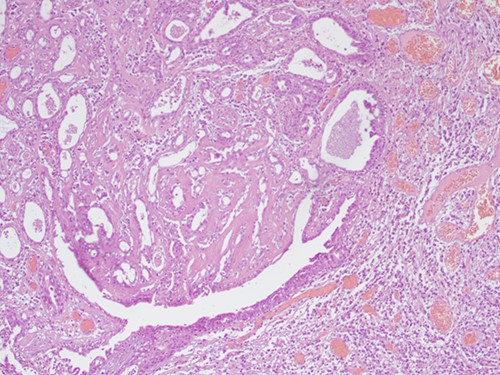

The histopathological examination found cystic invaginations of the infundibular epithelium projecting into the dermis, covered by a double cell layer (Fig. 2), proliferation of glands with prominent papillary architecture (Fig. 3) and fibrous cores containing numerous stromal plasma cells (Fig. 4). Other findings include verrucous (papillomatous) epidermal hyperplasia with hyperkeratosis and hypergranulosis (Fig. 5), irregular duct-like structures and cystic spaces (Fig. 6) and glands with double layer of cuboidal columnar epithelium and numerous stromal plasma cells (Fig. 7). These findings are compatible with Syringocystadenoma papilliferum with no signs of malignancy.

H&E staining 10× magnification. Proliferation of glands with prominent papillary architecture.